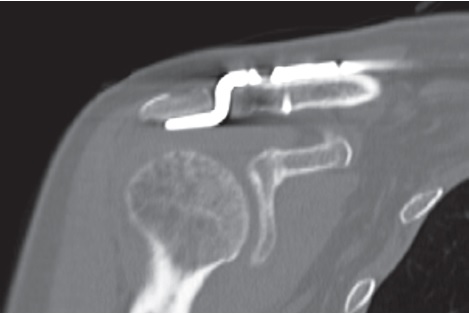

Послеоперационный период протекал без особенностей. Пациентка выписана на амбулаторное лечение на 5-е сут. со дня операции. Правая верхняя конечность была фиксирована косыночной повязкой на 4 нед. с момента оперативного лечения. Дальнейшее восстановление протекало по стандартному реабилитационному протоколу. Спустя 12 нед. пациентке была выполнена КТ области оперативного вмешательства, на которой были отмечены КТ-признаки консолидации как отломков акромиального конца ключицы, так и основания клювовидного отростка лопатки (рис. 3).

Рис. 3. КТ правого плечевого сустава через 3 мес. после операции: КТ-признаки консолидации отломков акромиального конца ключицы и основания клювовидного отростка лопатки

Fig. 3. Right shoulder CT scan 3 months after surgery. CT signs of bone union of the distal clavicle and coracoid process